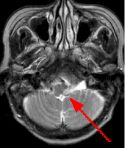

Fig. 1 Fig. 2 Fig. 3 Fig. 4

MRI Findings: In the supratentorial regions, some atrophy and chronic small vessel deep white matter ischemic changes were observed (Fig. 1) but no acute lesion or infarct was observed on MR diffusion. In the posterior fossa, however, a subtle small 1 cm hyperintensity can be seen in the left side of medulla on T2 weighted (Fig. 2) and FLAIR images (Fig. 3). This can be seen with an infarct, but its age would remain indeterminate. The MR diffusion image (Fig. 4) shows hyperintensity in the same region consistent with an acute infarct (arrows) as opposed to chronic ischemic changes.